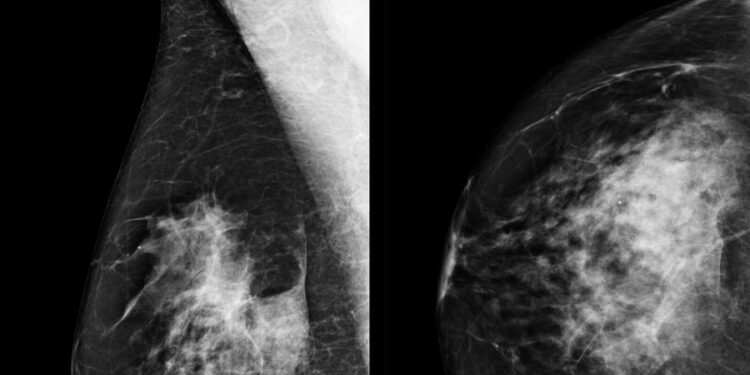

Një studim i bërë së fundmi arrin në përfundimin se mjekët janë në gjendje të zbulojnë kancerin në gji më shpesh në rastet kur përdorin inteligjencën artificiale për të ndihmuar në leximin e rezultateve të mamogramit. Siç njofton korrespondentja Dora Mekouar, inteligjenca artificiale po ndihmon në zbulimit të kancerit të gjirit, duke e rritur shkallën e zbulimit në mbi 17 për qind.

Kur mjekët përdorën inteligjencën artificiale për të analizuar mamogramet e mbi 460,000 grave në Gjermani, ata arritën të zbulojnë një rast më shumë kanceri për çdo një mijë gra, krahasuar me rastet kur analizoheshin vetëm nga mjekët, sipas hulumtuesve. Studimi i publikuar në revistën ‘Nature Medicine” është studimi më i madh i realizuar ndonjëherë, me të dhëna konkrete të pacientëve për ndikimin e përdorimit të inteligjencës artificiale në zbulimin e kancerit të gjirit.